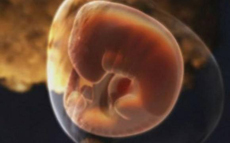

有的準(zhǔn)媽媽當(dāng)發(fā)現(xiàn)自己懷孕的時(shí)候,已經(jīng)有兩個(gè)月了,兩個(gè)月的胎寶寶還很小很小,不過(guò)卻真真實(shí)實(shí)存在于媽媽的體內(nèi)!那么,懷孕兩個(gè)月胎兒有多大?發(fā)育成什么樣子了?...